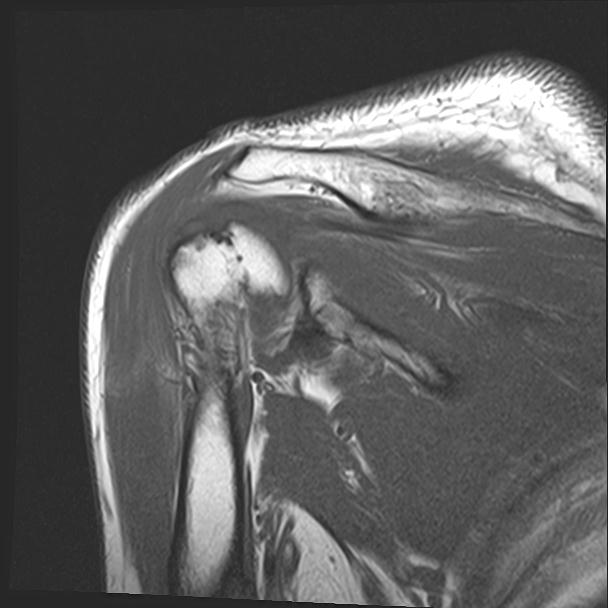

60058 3/9 11/4 右肩 2R+MRI 73歳男性 肩腱板損傷